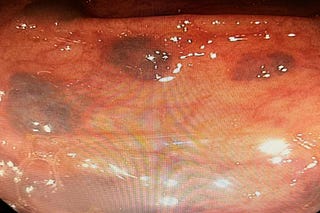

Advanced Endoscopic Imaging: The Quest for Virtual Histology

The Promise of Seeing What Only the Microscope Can See